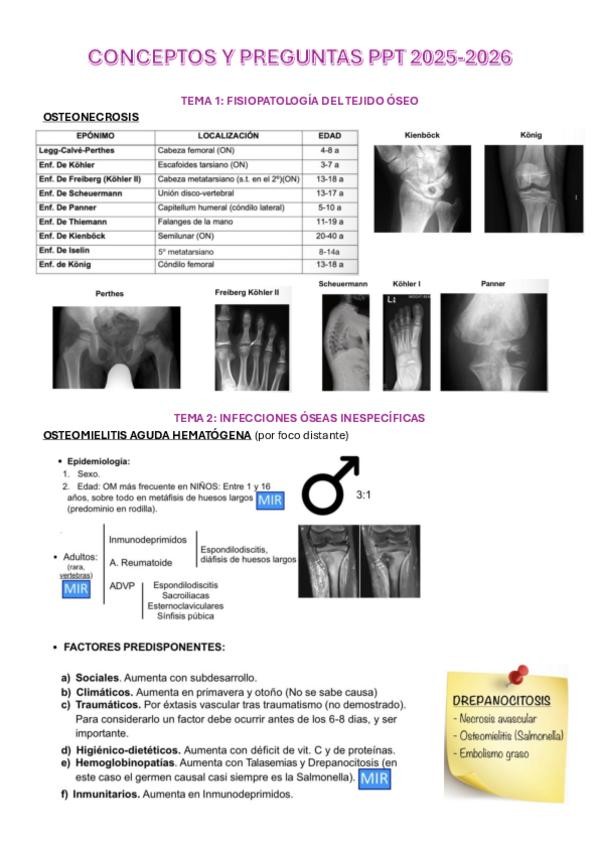

He publicado nuevos apuntes de 4º Traumatología: CONCEPTOS-Y-PREGUNTAS-PPT-2025-2026.pdf